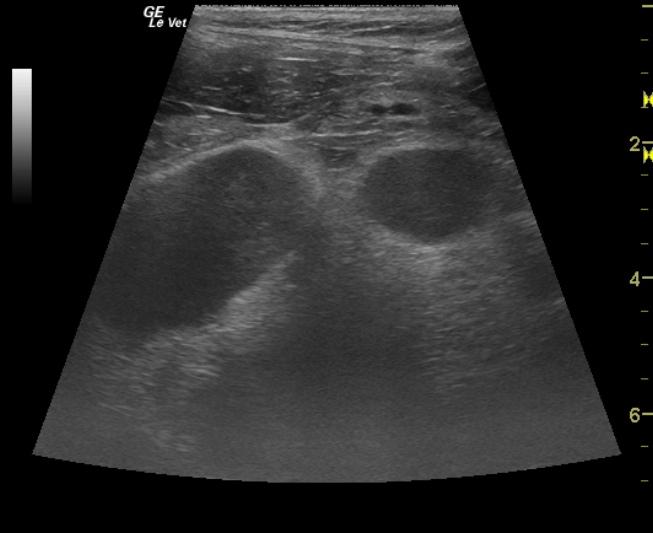

The gastrointestinal tract was normal in the region of the stomach and pylorus. The distal small intestine and jejunum presented minor areas of loss of detail with reactive omentum and large dramatically hypoechoic mesenteric root lymph nodes with significant loss of detail. Reactive omentum was also present suggestive of transmural pathology within the intestine and lymph nodes. The largest lymph node measured approximately 8cm in length.

Sampling

lossoflayeringLymphnodes